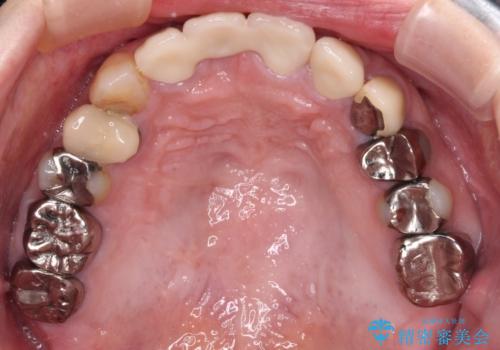

歯肉移植により歯肉ラインや歯の形態を整えることができ、ブリッジによる補綴としたことで舞えば全体の色調を整えることができました。